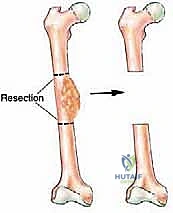

بسبب هذا التكوين التشريحي، اكتشف جراحو العظام المجهرية أنه يمكن استئصال جزء كبير من الجزء الأوسط من عظمة الشظية (يصل طوله أحياناً إلى 25 سم) دون التأثير بشكل كبير على قدرة المريض على المشي أو الوقوف.

1. استئصال الأورام العظمية (Bone Tumors)

عند إصابة المريض بورم عظمي خبيث أو حميد شرس (مثل الساركوما العظمية)، يتطلب العلاج استئصال الورم مع مسافة أمان من العظم السليم لمنع انتشار السرطان. هذا يترك فجوة عظمية هائلة. استخدام الشظية الوعائية يسمح بإعادة بناء الطرف بدلاً من بتره.